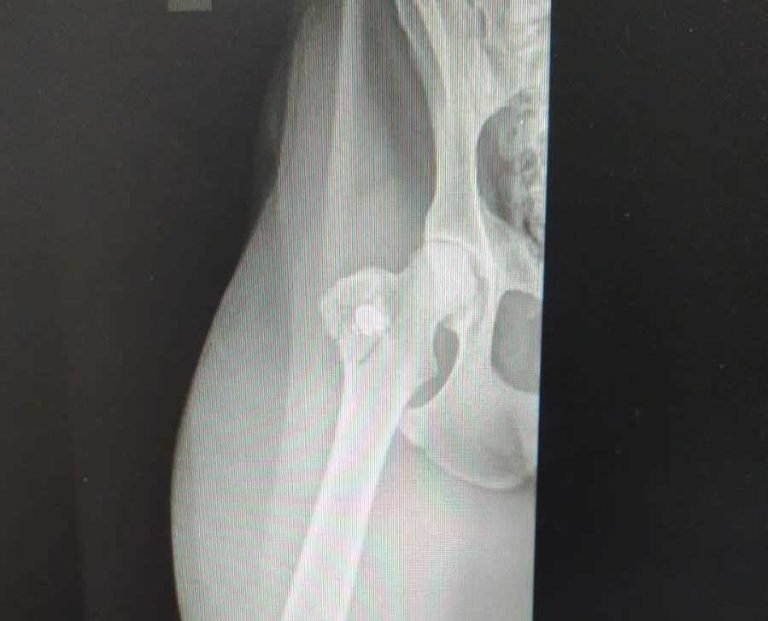

Homem é preso em flagrante por maus-tratos após atirar em cão